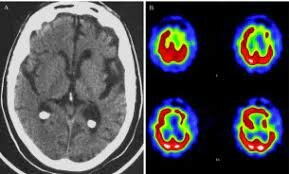

• Surgimiento de Imágenes cerebrales

Surgimiento de Imágenes cerebrales